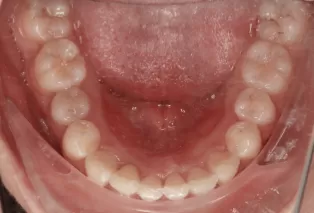

Female, 25 years old. Chief complaint: protruding and misaligned teeth, requiring orthodontic treatment.

Intraoral photos

Before Treatment